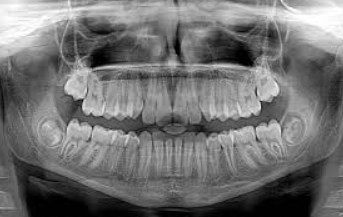

Diagnostic measures may include: routine x-rays; dental x-rays; and computed tomography (CT) scans.